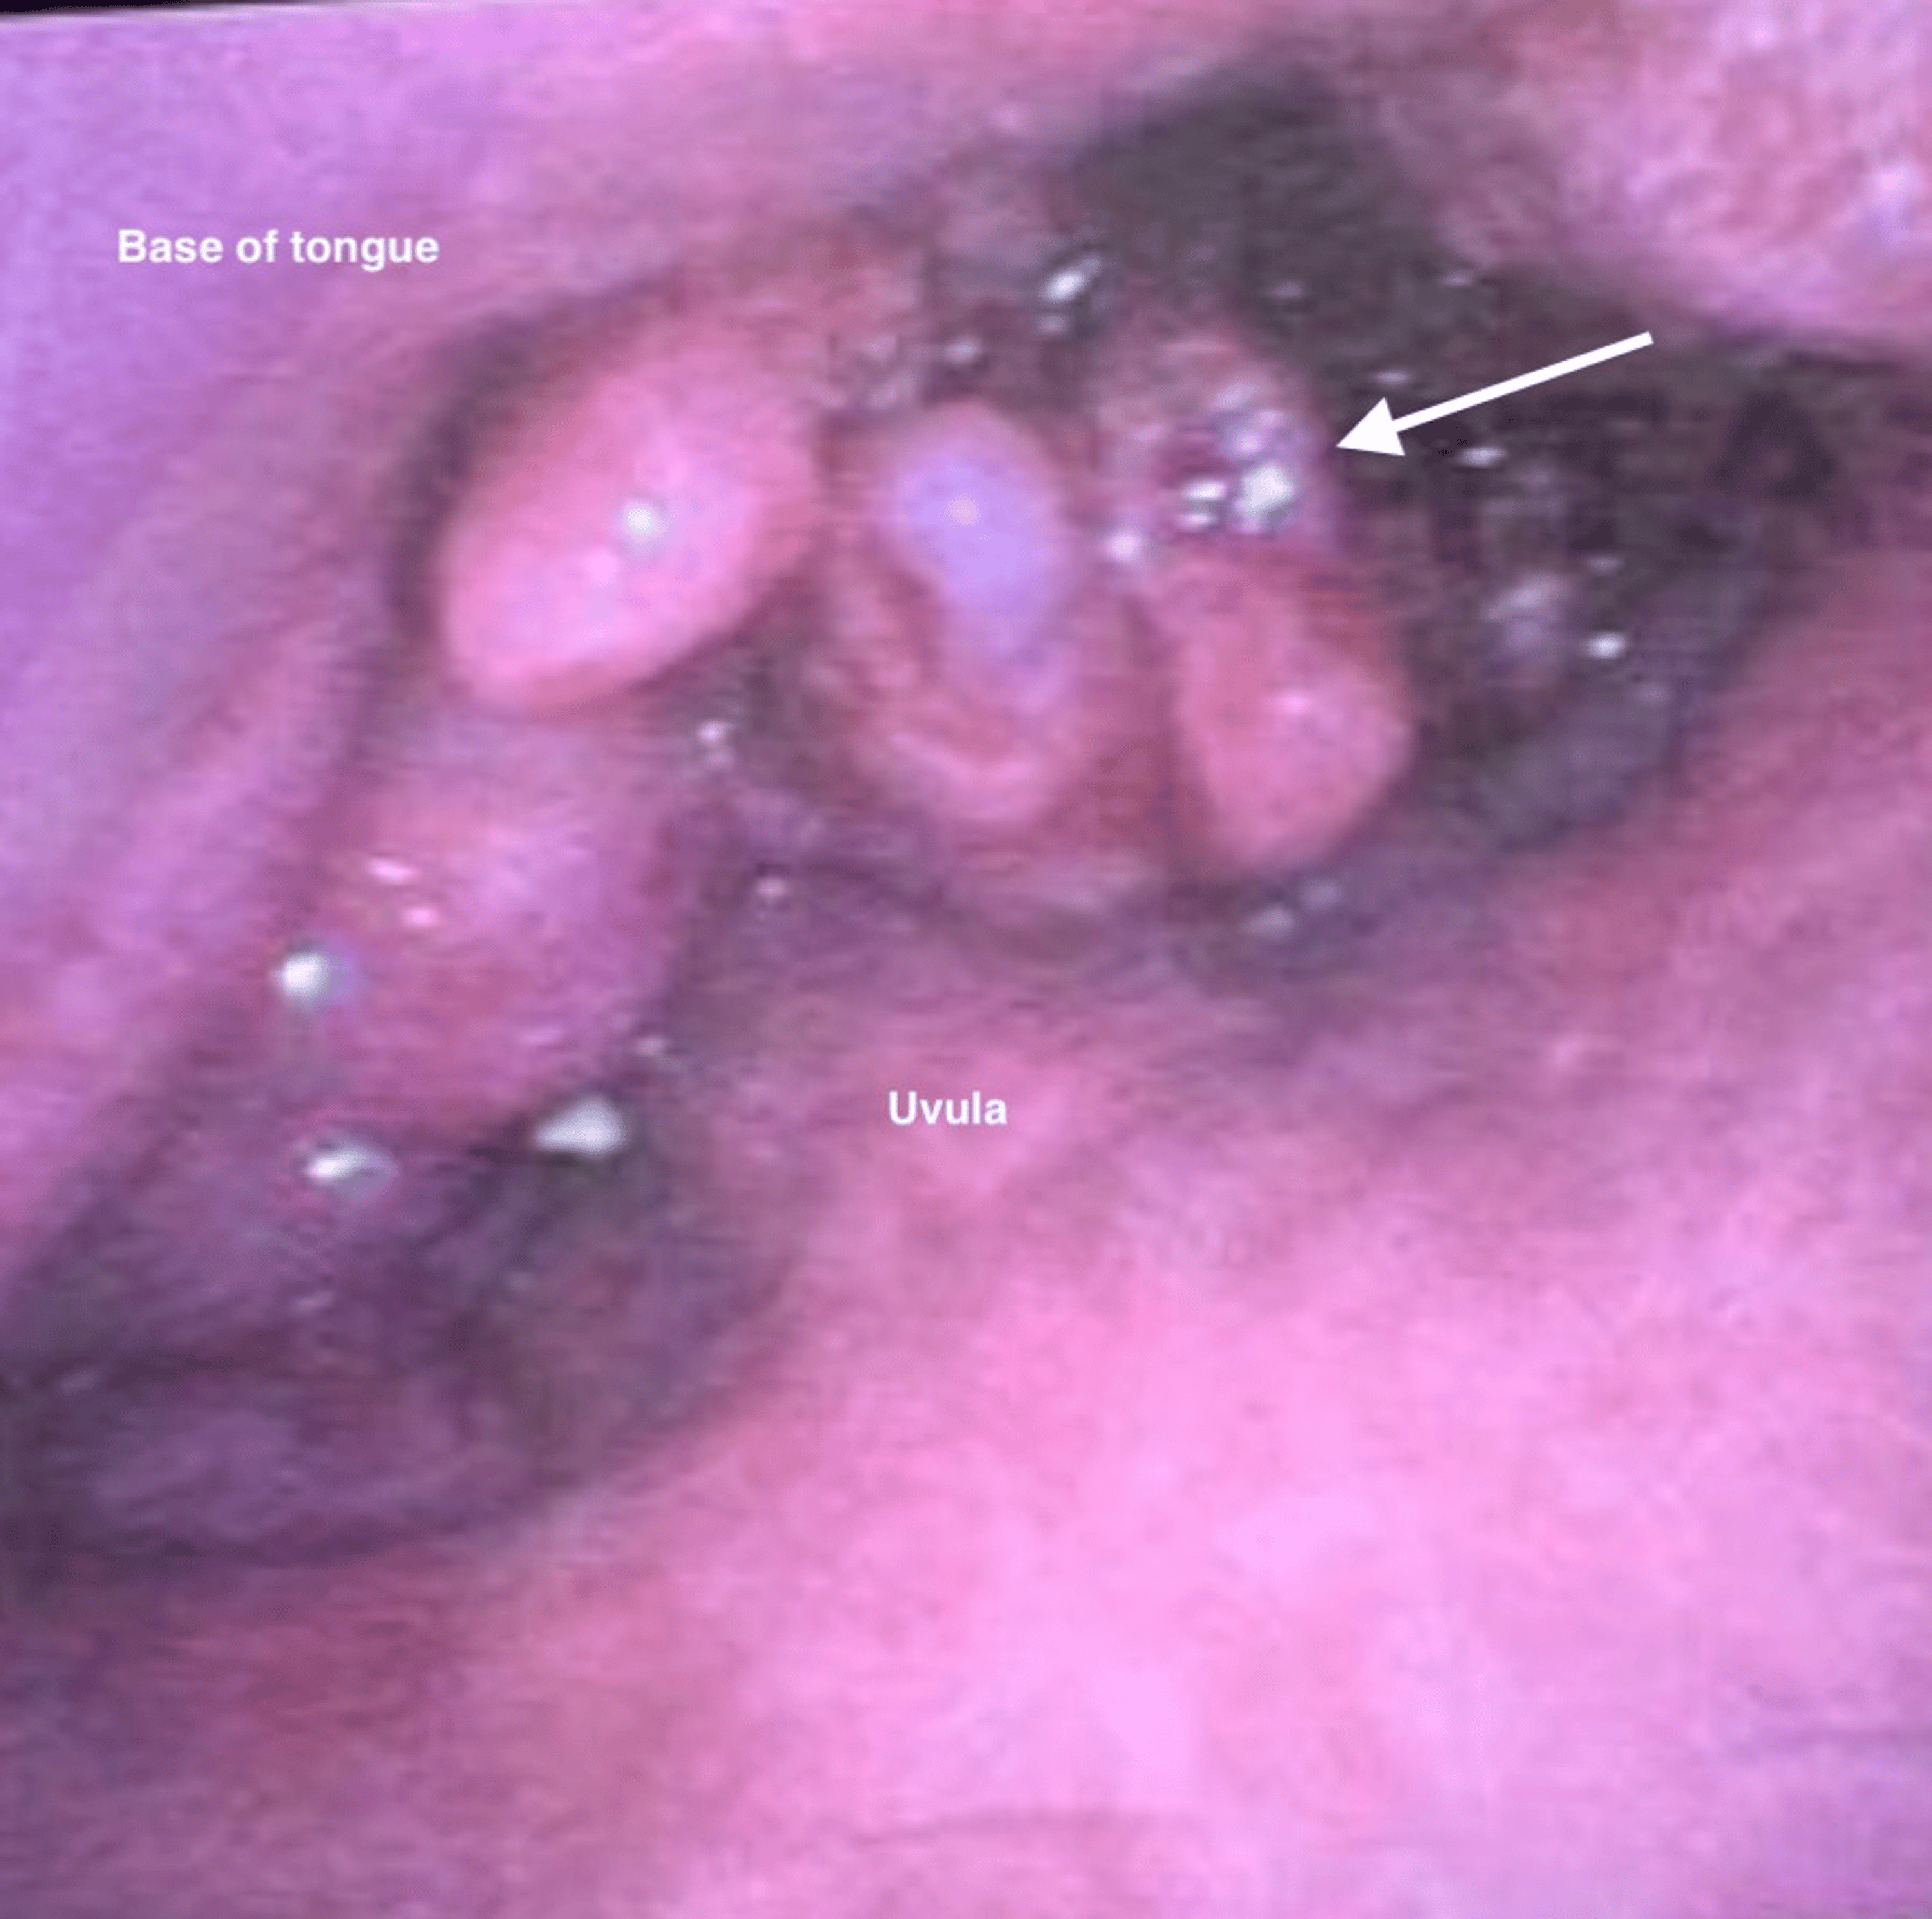

Fiberoptic bronchoscopy revealed a large exophytic tongue base tumor encompassing the entire posterior one-third of the tongue (Figure 6).

Airway topicalization was performed using the above-described approach (as previously depicted in Figure 2), resulting in smooth awake oral intubation with a size 7 ETT on the first attempt. Total lignocaine dose used for topicalization was 6 mg/kg.